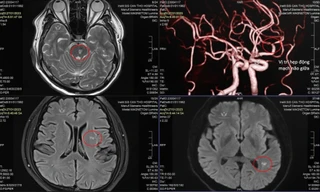

TPO - Nhập viện với chẩn đoán bị nhồi máu não bán cầu trái, yếu liệt nửa người. Qua kiểm tra hình ảnh, bác sĩ phát hiện ngoài tình trạng bị nhồi máu não, bệnh nhân còn có nguy cơ vỡ túi phình dẫn đến xuất huyết não.